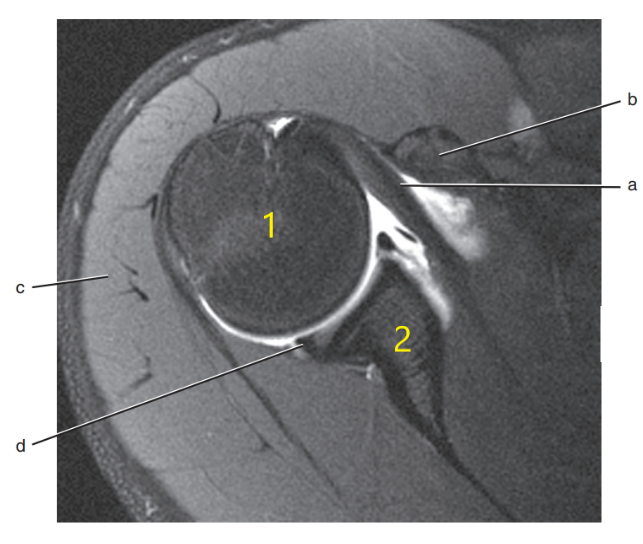

What is 1 ?

humeral head

What is D ?

supraspinatus tendon

glenoid labrum

What is c ?

lateral meniscus

acromion process

What is b ?

supraspinatus muscle